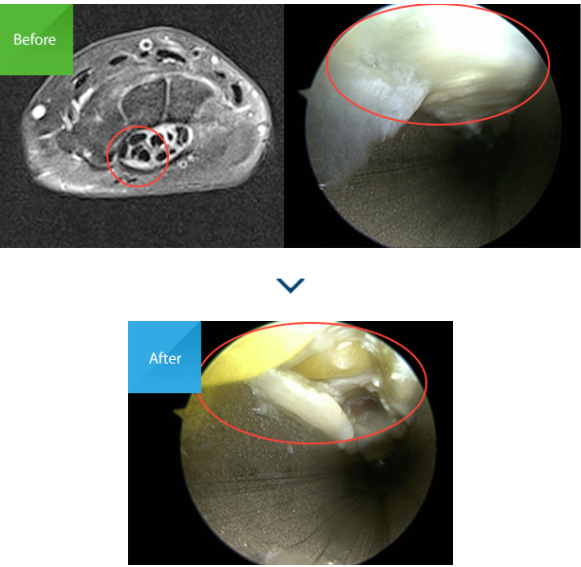

최근에는 초음파를 이용해 신경압박 정도 및 수술 후의

경과를 보기도 하며, 손목터널증후군의 원인 중 하나인

수근관 내 결절종 등 공간점유병소를 확인하기 위해

MRI를 이용하는 경우도 있습니다.